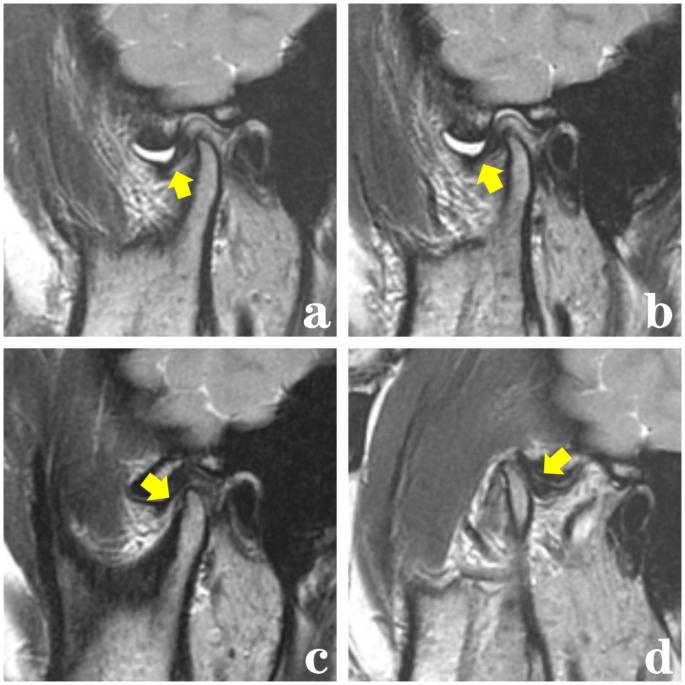

Among the 35 patients who underwent successful treatment, 24 cases achieved a normal disc-condylar relationship (Fig. 6), while 11 cases reverted to ADDwR (Fig. 7). According to Table 2, after 6 months of treatment, the condylar position moved significantly forward from its initial position (P < 0.001), while the disc on the affected side shifted significantly backward (P < 0.001).

T2-weighted MRI images reveal that patients with acute anterior disc displacement without reduction have restored a normal disc-condylar relationship after treatment. (a) Before treatment, the MRI showed anterior displacement of the disc and joint effusion in the closed-mouth position. (b) Before treatment, the sagittal MRI showed that the disc was still anteriorly displaced in the opened-mouth position. (c, d) After 6 months of treatment, the sagittal closed (c) / opened (d) position shows the disc was repositioned. TMJ disc positions are indicated by the yellow arrows.

T2-weighted MRI images of patients with acute anterior disc displacement without reduction, who were treated and subsequently restored to anterior disc displacement with reduction. (a) Before treatment, the MRI showed anterior displacement of the disc and joint effusion in the closed-mouth position. (b) Before treatment, the sagittal MRI showed that the disc was still anteriorly displaced in the opened-mouth position. (c) After 6 months of treatment, the sagittal closed position shows the disc anterior displacement slightly. ( d) After 6 months of treatment, the sagittal opened position shows the disc was repositioned. TMJ disc positions are indicated by the yellow arrows.